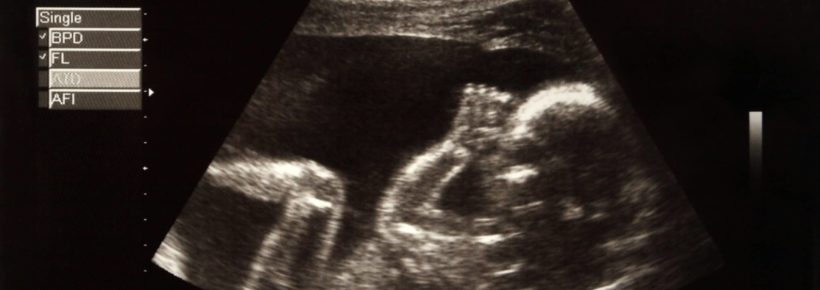

Take a moment to let that image fill your mind. These abortions are typically done in the second and third trimesters (13 weeks to full term), sometimes after the baby has reached viability. Because of improvements in medical interventions, a baby is viable between 22 and 24 weeks.